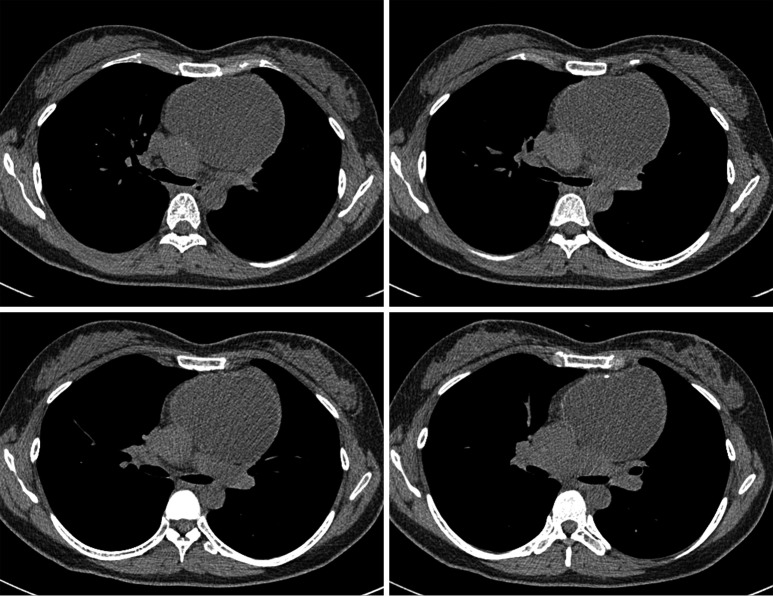

Figure 2.

Chest computed tomography scans show an anterior mediastinal mass causing extrinsic compression of the brachiocephalic vein to the posterolateral side (not shown). No airway compromise is shown at the level of the carina and main bronchi.